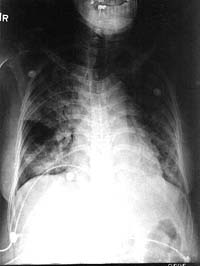

4 ngày sau khi phẩu thuật, bệnh nhân phát sốt và thở nhanh. Nghe phổi có ral nổ (crackles) hai bên toàn phế trường. X quang phổi cho thấy thâm nhiễm phế nang lan tỏa (hình 4). Công thức bạch cầu cho thấy 15.000 với Hb 8.2 và Hct 24.1%; cấy đờm cho kết quả vài cầu khuẩn gram dương và cấy máu âm tính. Bệnh nhân tiến triển suy hô hấp cấp và phải đặt ống cho thở máy. Khí máu cho kết quả pH 7.28, pCO2 là 40, pO2 là 105 trên70% FIO2 phải trợ thông khí. Điều trị kháng sinh phổ rộng diệt vi khuẩn kỵ khí cũng như các loại vi khuẩn không điển hình thương gây nhiễm trùng cơ hội. Mẫu bệnh phẩm đờm được nhuộm và nuôi cấy để đánh giá có khả năng là Pneumocystis, Strongyloides, Cryptococcus, hay nhiễm Mycobacterium. Phân tích huyết thanh học với kháng nguyên Cryptococal và kháng thể coccidioidal antibodies được thực hiện dựa theo quy trình sàng lọc nước tiểu đối với kháng nguyên của chủng Legionella.

Mặc dù kết quả của tất cả đều âm tính qua 3 ngày nuôi cấy và xét nghiệm, bệnh nhân vẫn diễn biến suy hô hấp, đòi hỏi phải xử trí an thần và mức FIO2 lên đến 100% (hình 5). Phế trường hai bên phổi cho thấy tăng thâm nhiễm ở các phế nang. Vì tình trạng của bà ta quá kém, bệnh nhân đã xuất huyết và xuất tiết tự phát và nổi vết ban đỏ trên bụng. Mặc dù tốc độ lắng máu bình thường, sự tiến triển của viêm phổi do lupus ban đỏ với các biểu hiện viêm mao mạch dưới da là có khả năng. Vào lúc này, một mẫu đờm dương tínhvới ấu trùng Strongyloides stercoralis và bệnh nguyên cuối cùng đã rõ (hình 6). Tiếc thay, đã quá muộn và khi cho liệu pháp khởi đầu ivermectin (200 ug/kg mỗi ngày) và thiabendazole (25 mg/kg mỗi ngày), bệnh nhân đã ngừng phổi ngừng tim và không đáp ứng với hồi sức tích cực. Chẩn đoán cuối cùng là Hội chứng tăng nhiễm do giun lươn (Strongyloides hyperinfection syndrome) dẫn đến viêm phúc mạc, suy hô hấp và tử vong.